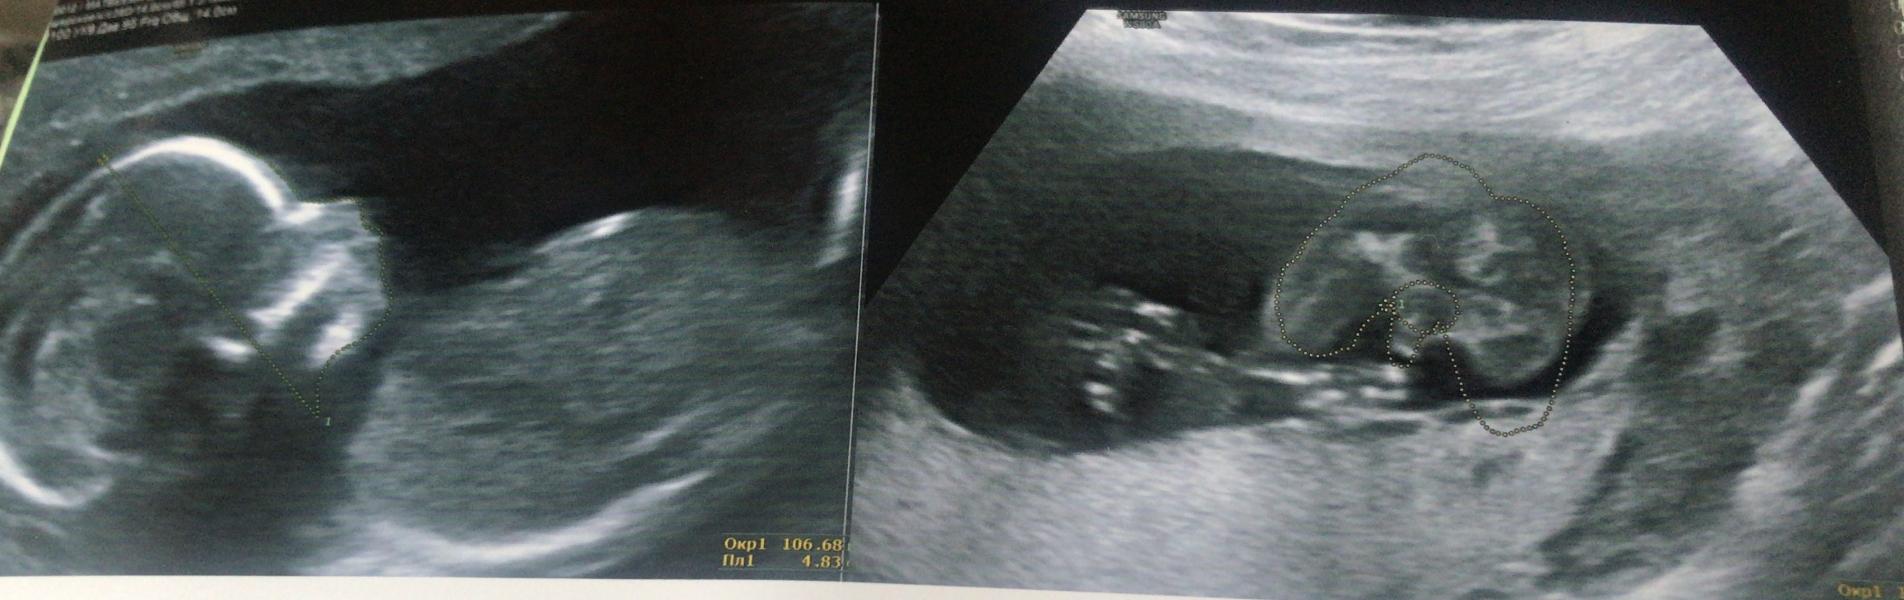

Ходили сегодня на узи (26.04.2022) в Кулик к Тыщенко А. Г

У нас будет сын 😍😍😍

Пол подтвердили

Чсс 152 удара